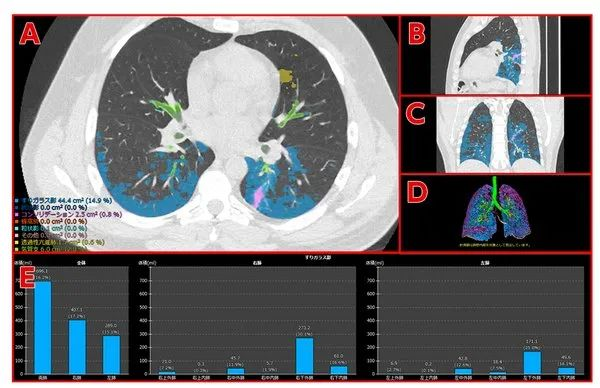

(上图为开发中的画面)新型冠状病毒肺炎患者的CT图像及分析结果

A-D分别显示病变识别结果:

A:横断位;

B:矢状位;

C:冠状位;

D:三维图像

E:以图表的方式显示指定病变所在区域和病状程度。